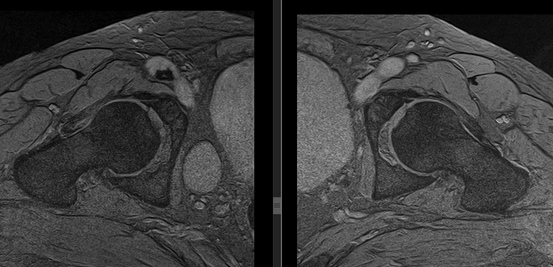

(Слева) МР-артрография, Т1 ВИ, режим подавления сигнала от жира, косой аксиальный срез: у балерины 16 лет определяется дефект хряща как спереди, так и сзади.

(Справа) МР-артрография, PDBИ, режим подавления сигнала от жира, сагиттальный срез: определяются дефекты хряща на всю его глубину в области вертлужной впадины и головки бедренной кости. Подрежающий кортикальный спой головки бедренной кости неровный. Сравните с нормальным хрящом, формирующим ободок однородной интенсивности сигнала вокруг суставных поверхностей.